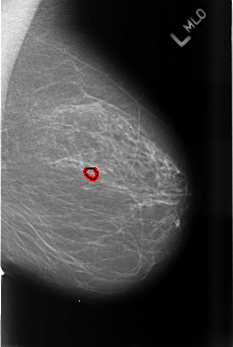

Digital Database for Screening Mammography

Volume: benign_14 Case: B-3467-1

B_3467_1.LEFT_MLO

LEFT_MLO LINES 4504 PIXELS_PER_LINE 3024 BITS_PER_PIXEL 12 RESOLUTION 50 OVERLAY

FILE: B_3467_1.LEFT_MLO.OVERLAY

TOTAL_ABNORMALITIES 1

ABNORMALITY 1

LESION_TYPE CALCIFICATION TYPE PUNCTATE-PLEOMORPHIC DISTRIBUTION CLUSTERED

ASSESSMENT 4

SUBTLETY 3

PATHOLOGY BENIGN

TOTAL_OUTLINES 1